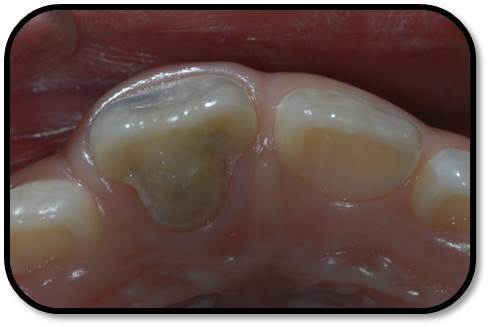

儿童7岁半,男 主诉:右上前牙自发痛,咬合痛3天。 现病史:患儿右上前牙自发痛,咬合痛3天,牙龈肿痛1天,今来诊求治。否认前牙外伤史。 既往史,家族史:无特殊 全身情况:健康

检查: 右上1牙冠略宽大,舌侧见粗大的畸形舌尖,叩痛(++),松Ⅰ°,唇侧牙龈红肿前庭沟膨隆扪痛,挤压唇侧龈缘溢脓,冷热测无反应,右侧上下1侧方颌,正中颌颌创伤。 X线:右上1发育7-8期,根管平行状,根尖孔宽大,约5-6mm宽,根尖周低密度影。髓腔根管宽大内见倒置牙影像,倒置牙可见髓腔。 余牙未见异常 6均已萌出建颌

初步诊断:右上1牙内陷根尖炎,颌创伤 治疗计划:1、口腔卫生宣教 2、右上1调合,牙髓再血管化治疗, 成年后烤瓷贴面修复 3、定期复查(1月、3月、6月--) 处置:右上1STA必兰局麻下舌侧开髓,查得两根管,一个是长扁根管,一个是牙中牙内陷盲袋形成的椭圆根管,拔根髓不成形,5.25%次氯酸钠冲洗浸泡根管5-10分钟,超声根管荡洗,反复3次,2%CR冲洗根管,隔湿干燥后,封Ca(OH)2。调合,去除咬颌创伤。 复诊:隔2周复诊,行5.25%次氯酸钠冲洗浸泡根管5-10分钟,超声根管荡洗,反复3次,2%CR冲洗根管,隔湿干燥后,封Ca(OH)2。 此后复诊每隔1周行2.5%次氯酸钠冲洗浸泡根管5-10分钟,超声根管荡洗,反复3次,2%CR+NS冲洗根管,隔湿干燥后,封Ca(OH)2。 2个月后:患牙症状消失,临床检查无阳性体征,去暂封无渗出,2.5%次氯酸钠冲洗浸泡根管5-10分钟, 2%CR+NS冲洗根管,隔湿干燥后,用无菌30#根管锉超出根尖3-4mm刺破根尖组织出血,待形成血凝块后,置MTA,GIC,冠方树脂严密充填。